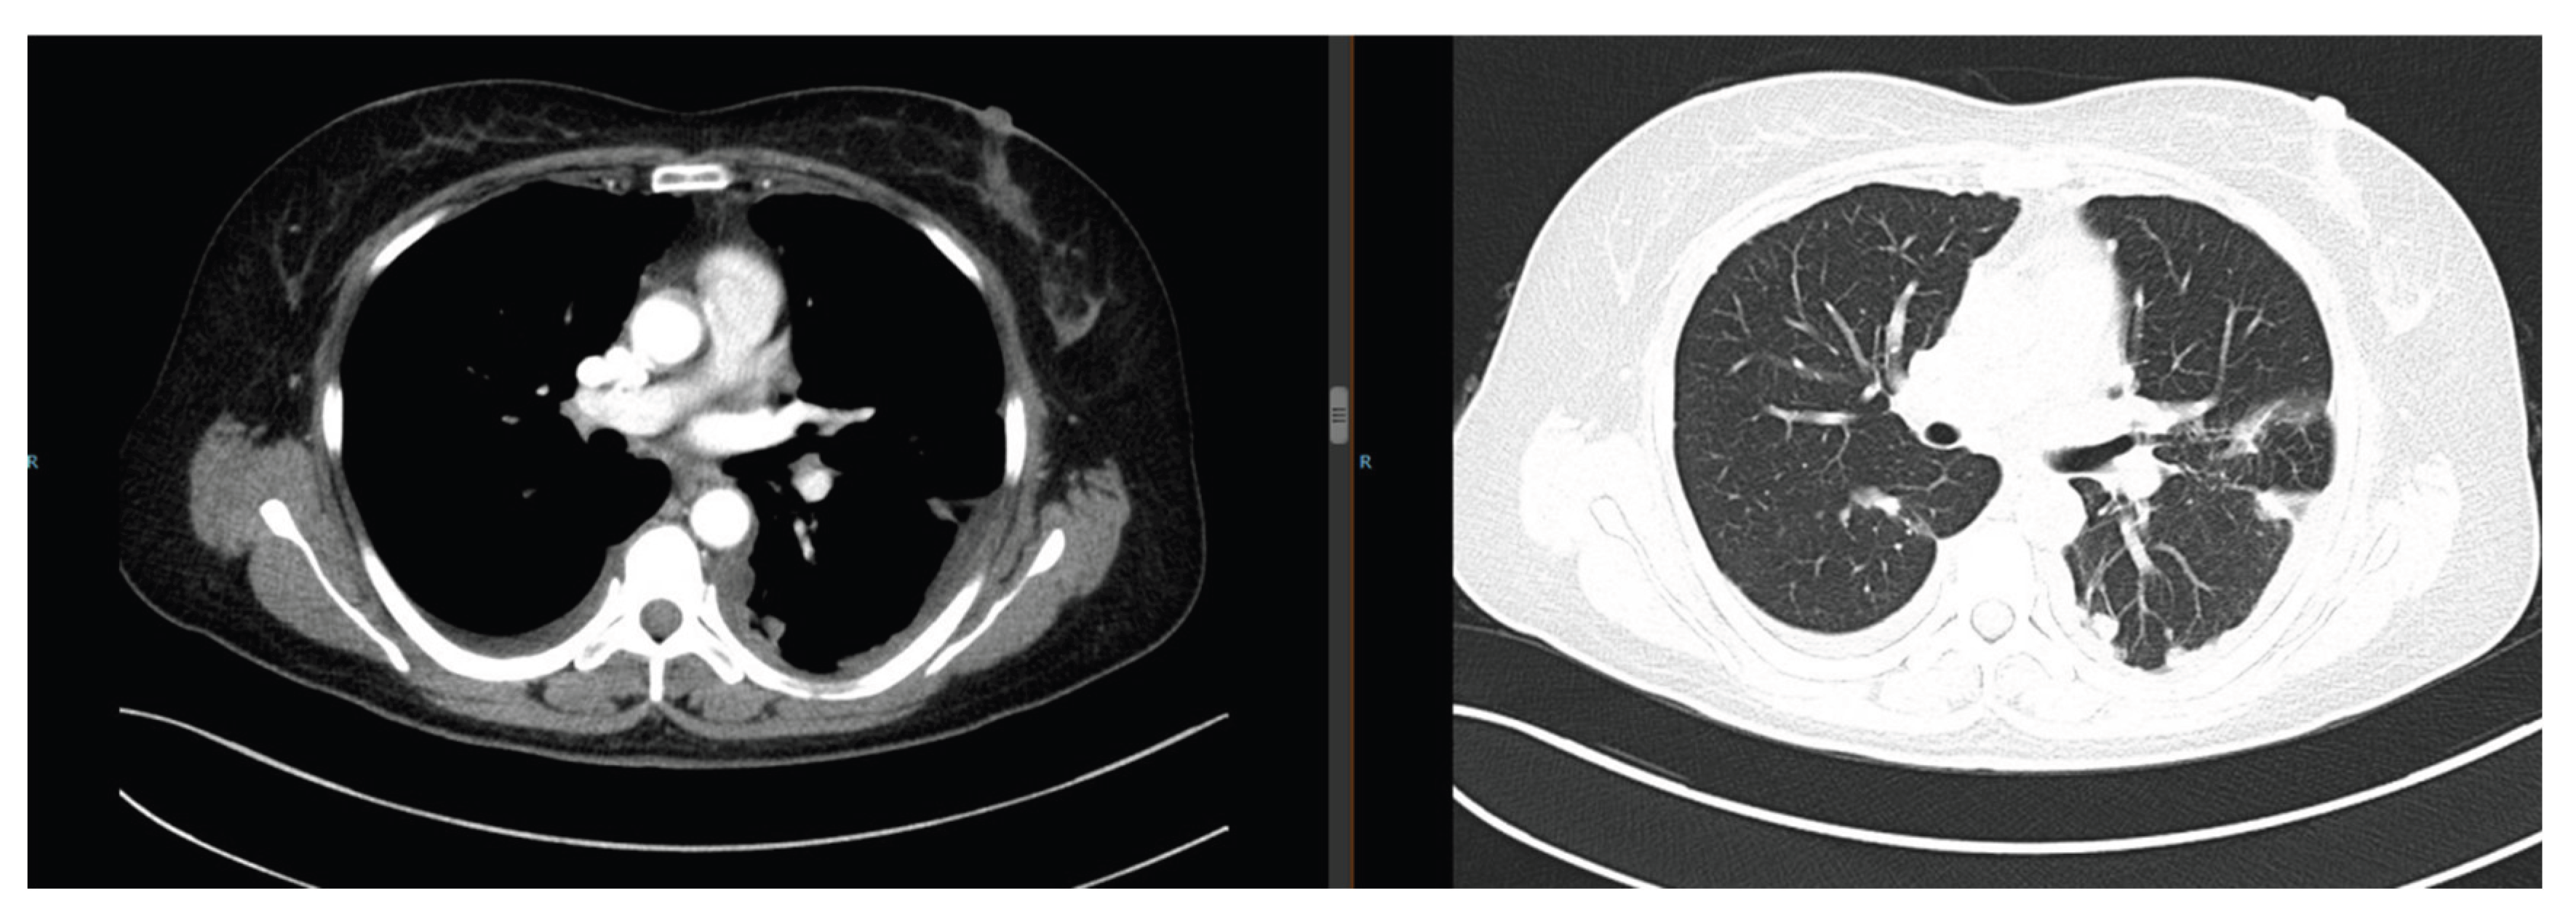

The patient presented with cough and expectoration. Chest computed tomography (CT) revealed multiple bilateral pulmonary nodules (maximum diameter: 3.5 cm) with moderate right pleural effusion (Figure 1). Pathological examination of the pleural effusion confirmed adenocarcinoma (Figure 2), and next-generation sequencing (NGS) detected an EGFR exon 19 deletion mutation. She was diagnosed with advanced lung adenocarcinoma (cT4N2M1 Stage Ⅳ). Treatment included the first-generation TKI gefitinib (250 mg orally once daily) and cisplatin intrapleural perfusion. Two months later, the pleural effusion completely resolved, and the pulmonary nodules reduced by 50%, achieving a partial response (PR) (Figure 3).

Figure 1. Chest CT on September 11, 2019: Multiple bilateral pulmonary nodules (maximum diameter 3.5 cm) with right pleural effusion.

Figure 3. Chest CT on February 13, 2020: Complete resolution of pleural effusion, 50% reduction in pulmonary nodules.